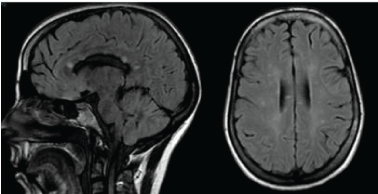

The first symptoms started two years before with dizziness and a facial palsy at the onset. She underwent a cerebral Magnetic Resonance (MRI) showing T2-weighted lesions, that were suggestive of multiple sclerosis (Figure 1). A lumbar puncture showed a normal Cerebrospinal Fluid examination (CSF) with no oligoclonal bands and no elevated IgG index. The initial diagnosis was remittent-recurrent MS, and she was treated with intravenous Methylprednisolone (MTP) pulses during five consecutives days, following with Interferon (IFN b1a) as the usual Disease Modifying Treatment (DMT). The symptoms did not improve. After two months she experienced sudden loss of vision in the left eye, so she was evaluated by an ophthalmologist. A visual field examination revealed a superior altitudinal defect in the left eye and a fundoscopy showed findings suggestive of retinal vasculitis. She was treated with oral corticosteroids and after that she remained neurologically stable.

Figure 1: Sagittal and axial FLAIR images showing callosal and deep white matter hyperintense lesions. View Figure 1